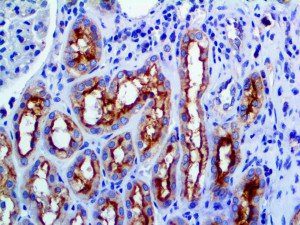

The first cytokines released are interleukin 1β (IL-1β) and tumor necrosis factor-α (TNF-α), which attract a variety of circulating white blood cells (WBCs) to the infection site, including neutrophils, monocytes, macrophages, and natural killer (NK) cells. This response, along with the antipathogenic chemicals released by these cells (i.e., complement), comprise the innate immune response. These cells directly attack the invading pathogen and also release additional cytokines, chief among them interleukin-1 and 6 (IL-6). IL-6 is essential for invoking the adaptive immune response, which calls T-cells, B-cells, and T helper (Th) cells to the infection site. IL-6 also stimulates further recruitment, proliferation and activation of macrophages.

It is the ICU physician who is most likely to witness one of the deadliest manifestations of the abnormal immunological response, the cytokine storm syndrome (CSS). This response is also referred to by some as the cytokine release syndrome (CRS). CSS is characterized by continuous activation and expansion of macrophage and lymphocyte populations, which secrete large amounts of cytokines, causing the cytokine storm. This massive cytokine release is akin to hemophagocytic lymphohistiocytosis (HLH) disease, a syndrome characterized by initial unchecked and persistent activation of cytotoxic T lymphocytes and NK cells.